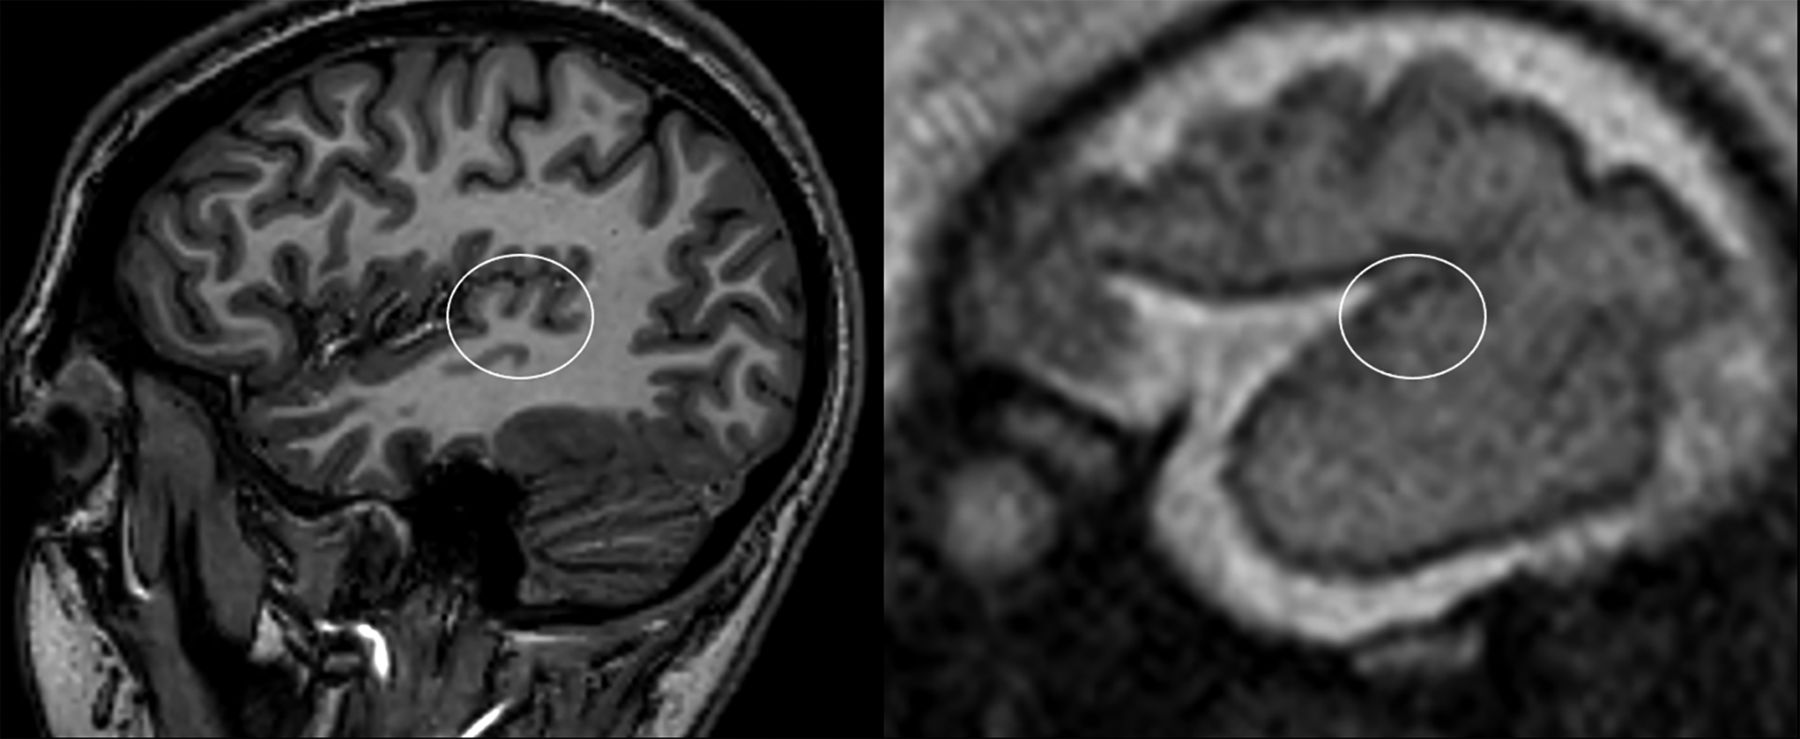

All MR images were analyzed in consensus by 2 neuroradiologists with >5 years' experience in prenatal neuroradiology. Postnatal HG landmarks were used as a reference on T2WI (Fig 1). On axial sections, the HG was visualized on the slice passing through the interthalamic adhesion as an oblique structure of the planum temporale with a posterior-anterior and medial-lateral dislocation.7,16 On sagittal and coronal sections, the HG appears as a protrusion above the posterior part of the superior temporal gyrus (Fig 1).4⇓-6

Representative images of adult (upper row) and fetal (lower row, 28 weeks' GA) HGs on the 3 orthogonal planes. Adult landmarks were used to correctly identify the HG on the fetal brains (asterisk).

The SI of the HG in representative adult (left) and fetal (right, 28 weeks' GA) brains. The characteristic adult heart-shaped configuration in the sagittal plane was used for SI identification on fetal scans.